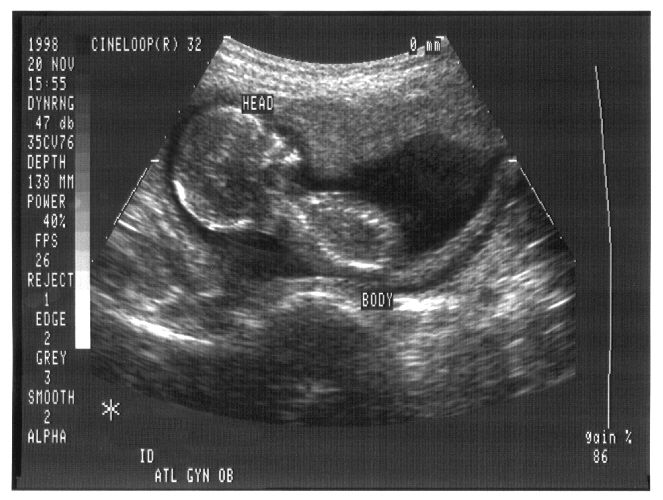

To add insult to injury, even science seems to be turning against abortion partisans. “modern prenatal imagery gives abortion opponents a new way to make their case.”